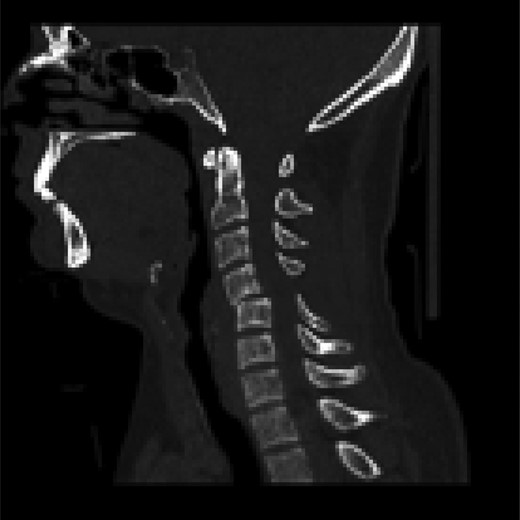

The patient was maintained in triple immobilization and a computed tomography (CT) scan was obtained, this revealed bilateral C4/5 facetal subluxation with no obvious fractures (Fig. 2).

Sagittal CT scan images showing a pure soft tissue bilateral C4/5 Subluxation with bilateral ‘Naked Facet’ sign.